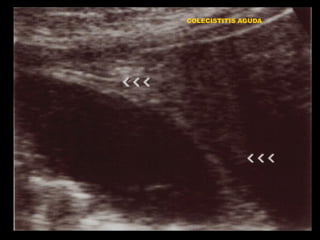

COLECISTITIS AGUDA

COLECISTITIS. PATRONES AL US

• PATRON EN TRES CAPAS

• PATRON ESTRIADO